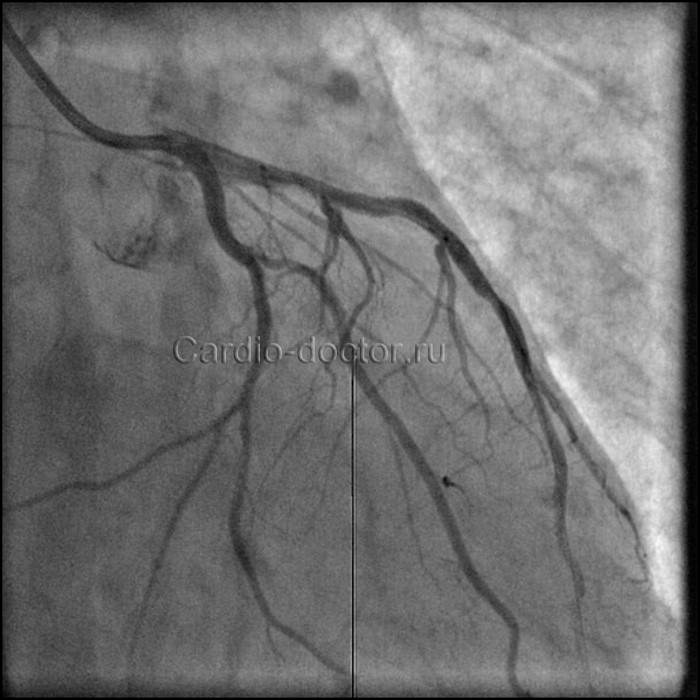

Как только стент полностью раскрывается до нужного размера, баллон сдувают. Давление в баллоне для полного раскрытия стента может доходить до 30 атмосфер, в среднем 10-18 атм. Для сравнения, в колесах автомобиля давление 2 атм. Производят контрольную коронарографию: вводят контрастное вещество в стентированный сосуд и оценивают степень восстановления его проходимости.

Как только стент полностью раскрывается до нужного размера, баллон сдувают. Давление в баллоне для полного раскрытия стента может доходить до 30 атмосфер, в среднем 10-18 атм. Производят контрольную коронарографию: вводят контрастное вещество в стентированный сосуд и оценивают степень восстановления его проходимости (кровотока).